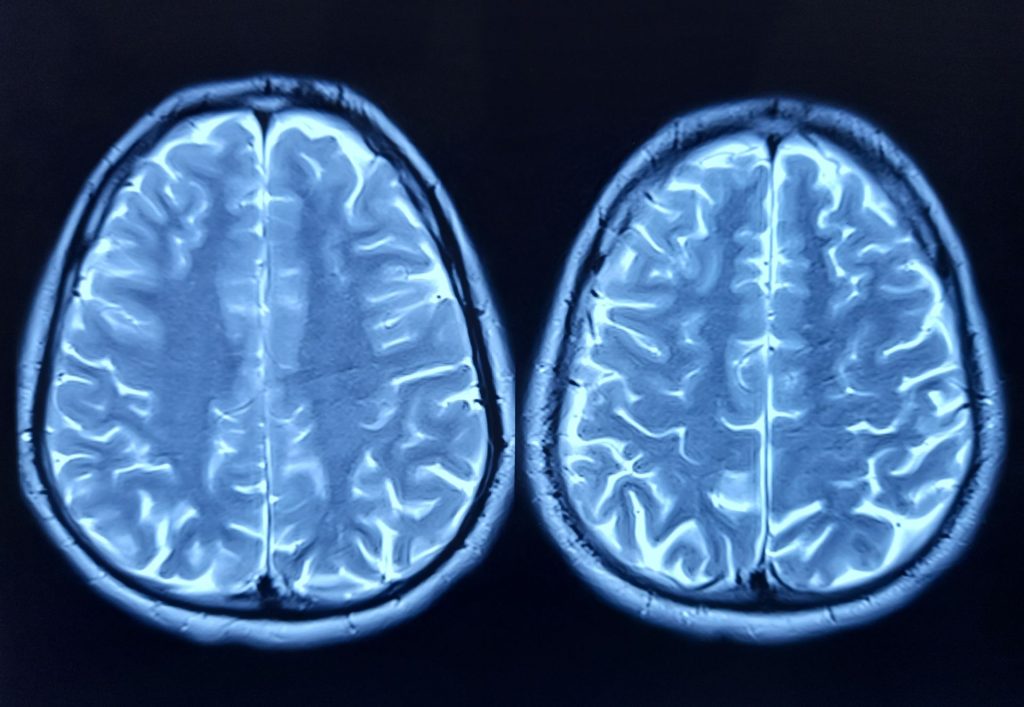

Cercetătorii au identificat o proteină, numită FTL1, care pare să joace un rol important în procesul de îmbătrânire a creierului. Studiile realizate pe șoareci arată că nivelurile ridicate ale acestei proteine pot slăbi conexiunile dintre celulele cerebrale, conducând la declinul memoriei. Descoperirea deschide noi perspective pentru dezvoltarea unor tratamente care ar putea încetini sau chiar inversa efectele îmbătrânirii asupra creierului. Îmbătrânirea afectează în mod semnificativ hipocampul, o regiune critică a creierului responsabilă de memorie și învățare. Oamenii de știință au analizat evoluția genelor și a proteinelor din hipocampul șoarecilor, concentrându-se pe schimbările care apar odată cu înaintarea în vârstă. Astfel, au observat că proteina FTL1 este constant prezentă în cantități mai mari la animalele mai în vârstă. Această constatare a fost corelată cu un număr mai mic de conexiuni neuronale și performanțe cognitive mai slabe.

Pentru a evalua impactul proteinei FTL1, cercetătorii au manipulat nivelurile acesteia la șoareci. Creșterea cantității de FTL1 la șoarecii tineri a dus la o deteriorare a funcțiilor cerebrale, simulând efectele îmbătrânirii. În contrast, reducerea nivelului de FTL1 la șoarecii bătrâni a condus la o îmbunătățire a memoriei și a conexiunilor neuronale. „Este cu adevărat o inversare a deficiențelor”, a declarat Dr. Saul Villeda, director adjunct al Institutului de Cercetare a Îmbătrânirii Bakar din cadrul UCSF și autor principal al studiului. Experimentele de laborator au arătat că FTL1 influențează modul în care celulele cerebrale utilizează energia. La șoarecii bătrâni, nivelurile ridicate ale proteinei FTL1 încetinesc metabolismul celular în hipocamp. Când cercetătorii au tratat celulele cu o substanță care stimulează metabolismul, efectele negative au fost prevenite. Aceste observații sugerează că FTL1 afectează în mod direct funcționarea creierului, influențând atât structura, cât și metabolismul celular.